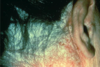

define purpura

Discoloration of the skin due to the presence of blood in the tissue, outside of blood vessels; will not blanch with pressure (example: vasculitis)

* the pinpoint lesions lower in the picture = petechiae

define petechiae

A punctate region of purpura (tiny dots)